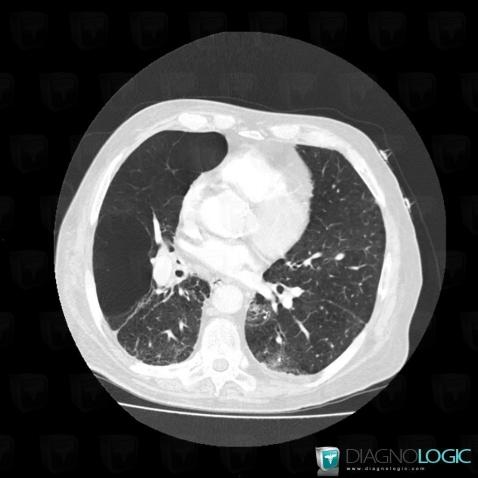

Emphysème lobaire géant, Parenchyme pulmonaire, Scanner

Voici les informations spécifiques à l'image clé ci dessus:

- Diagnostic Emphysème lobaire géant, Localisation(s) Parenchyme pulmonaire, comportant les gammes Poumon hyperclair unilatéral, Malformation pulmonaire congénitale, Lésions kystiques pulmonaires multiples